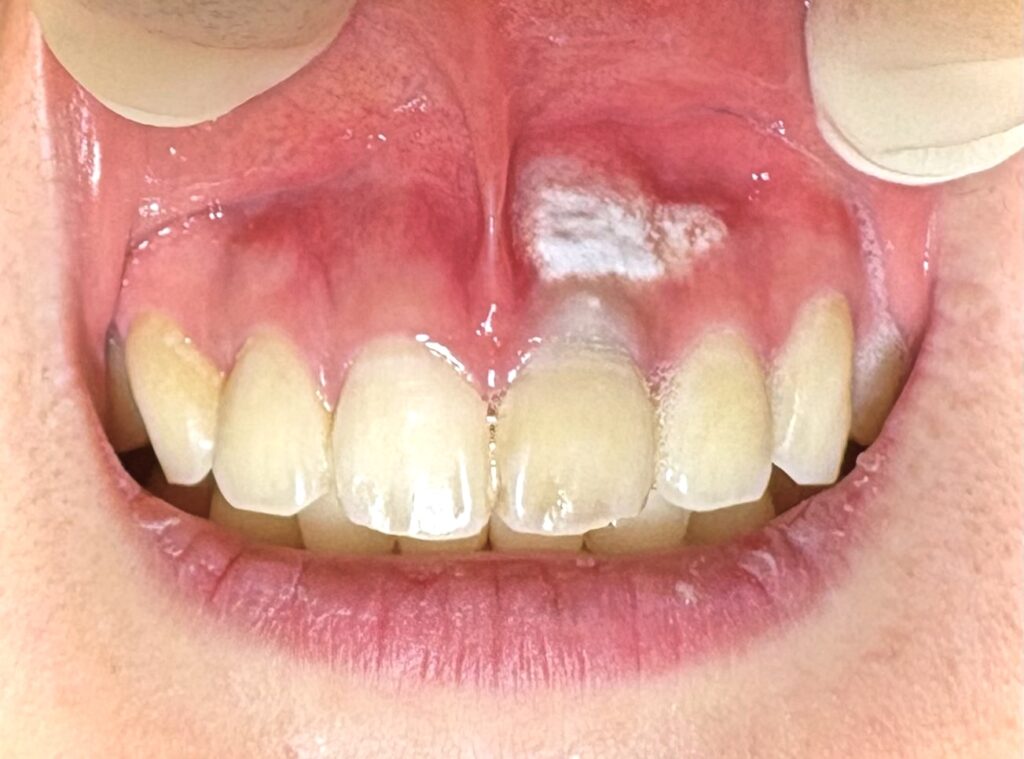

これが カタラーゼ反応陽性↓

歯茎に薬液をつけた時細菌がいると 泡がブクブク 出ます。

今回はこの反応が見られ、

内部に感染が残っている状態でした。